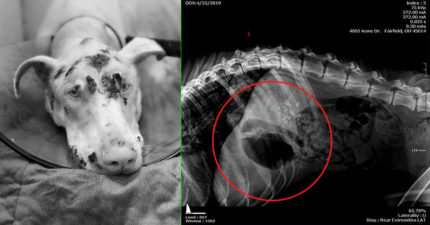

无良饲主「饿死爱犬」被判刑 照X光「装满巨石」网友:换他吃

世界, 动物